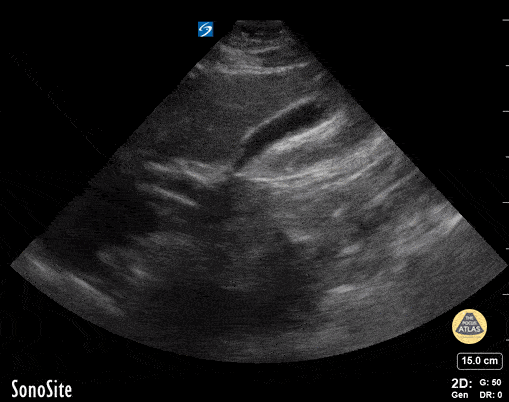

15 yo presents with abdominal pain. POCUS shows a gallbladder polyp of unknown significance, likely incidental finding. Contributor: Kathryn Pade, MD, Rady Children's Hospital San Diego